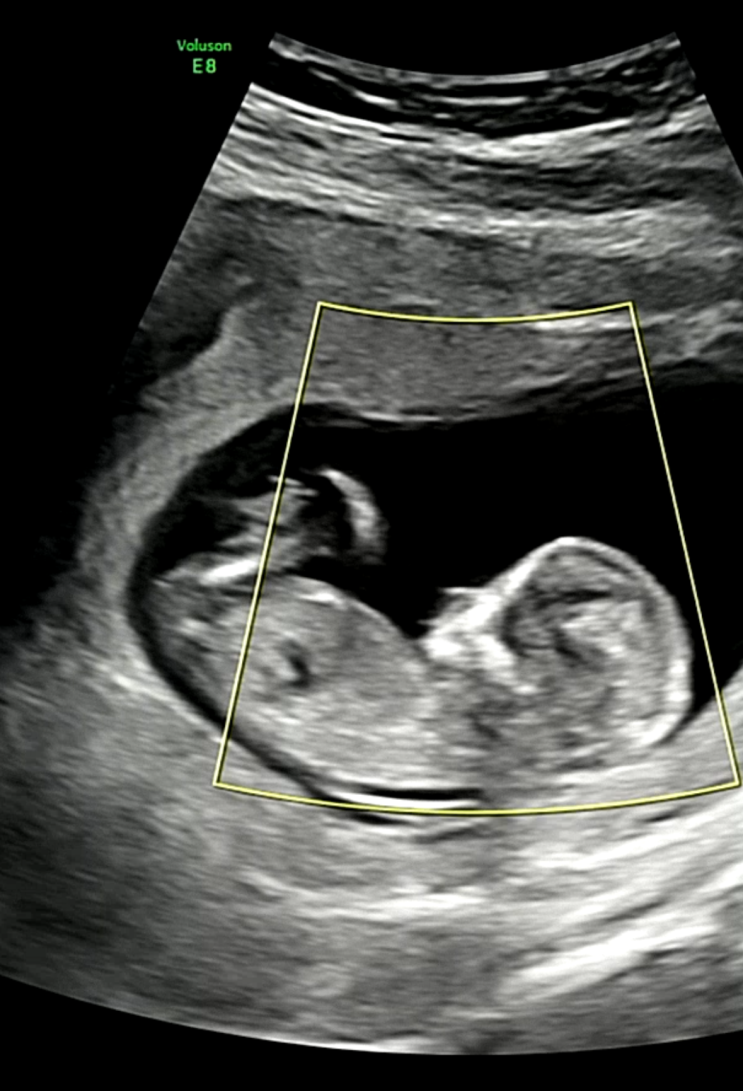

[중기] 16주~20주: 엣헴, 나도 이제 어엿한 임신 중기(16주 성별확정, 젠더리빌파티, 첫 태동, 열달후에 어플, 태아성장보고서)

병원 진료 갈 때마다 기록하려고 했는데 이거 참.. 쉽지가 않다..ㅎㅎㅎㅎㅎ 막상 쓰면 신나서 이거저거 다...